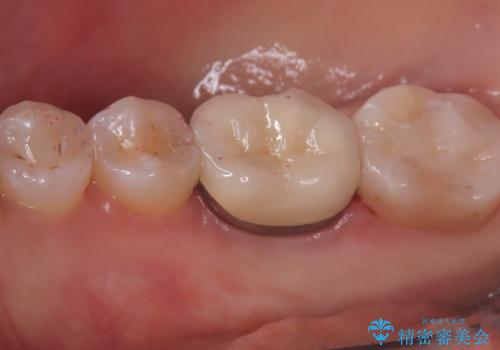

クリーニングにいらした患者さんで、右下7番目の歯の奥側の面や手前の歯との間にう蝕があり、噛む面にも蝕処置によるレジン材料が詰まっていたことから、う蝕も古い材料も全て除去しセラミックインレーでのやり替えとなりました。

右下7近遠心にカリエスを認め、咬合面のCR修復も劣化していたので、カリエスと古い材料を全て除去し新しくCR裏層した後、セラミックインレーをセットしています。セット時はラバーダム防湿を行っています。